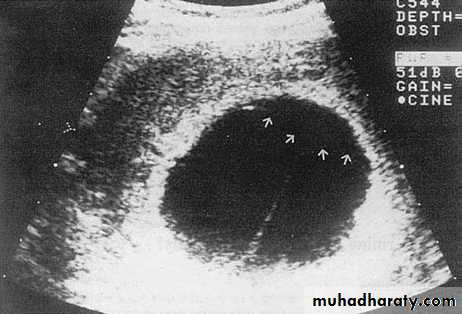

6.Amniotic fluid volume assessment

Ultrasound can be used to identify both increasedand decreased amniotic fluid volumes. The fetus has a role in the control of the volume of amniotic fluid.Fetal growth restriction can be associated with reduced amniotic

Amniotic fluid assessment

1-The maximum vertical pool of less than 2 cm suggest oligohydramnios, and measurements of greater than 8 cm suggest polyhydramnios.2-The Amniotic Fluid Index (AFI)

The AFI alters throughout gestation, but in the third

trimester it should be between 10 and 25 cm; values

below 10 cm indicate a reduced volume and those

below 5 cm indicate oligohydramnios, while values

above 25 cm indicate polyhydramnios.